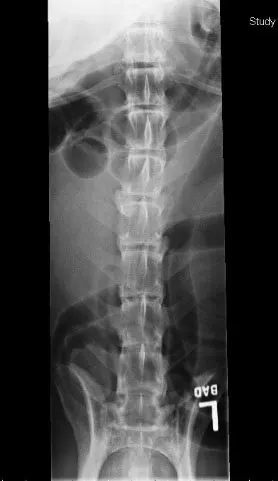

Lateral radiograph of a canine spine showing clear alignment of the vertebrae, with no signs of fractures or abnormalities. The surrounding soft tissue structures are also visible, providing context for the spinal anatomy.

Spondyloarthropathy (or osteoarthropathy) in dogs is a degenerative, age-related process involving the articular facets (click on PDF icon at the top to see the images with arrows). Performance animals may have pain and inflam­mation associated with these degenerative changes, but many dogs show no clinical signs. Treatment is similar to that used for arthritis of the appendicular skeleton.

Spondyloarthropathy is diagnosed radiographically by the presence of bony proliferation, sclerotic margins, and osteophytosis of the articular facets, and is not necessarily associated with ventral spondylosis deformans. Osteochondritis dissecans lesions or congenital hypoplasia of the articular facets (arrows) can also be seen in young dogs; although not commonly diagnosed, these findings (which can lead to spondyloarthropathy) may be underrecognized in patients that do not undergo advanced imaging studies. Myelography, computed tomography, or magnetic resonance imaging is indicated to determine if bony proliferation due to degenerative joint disease is causing spinal compression.